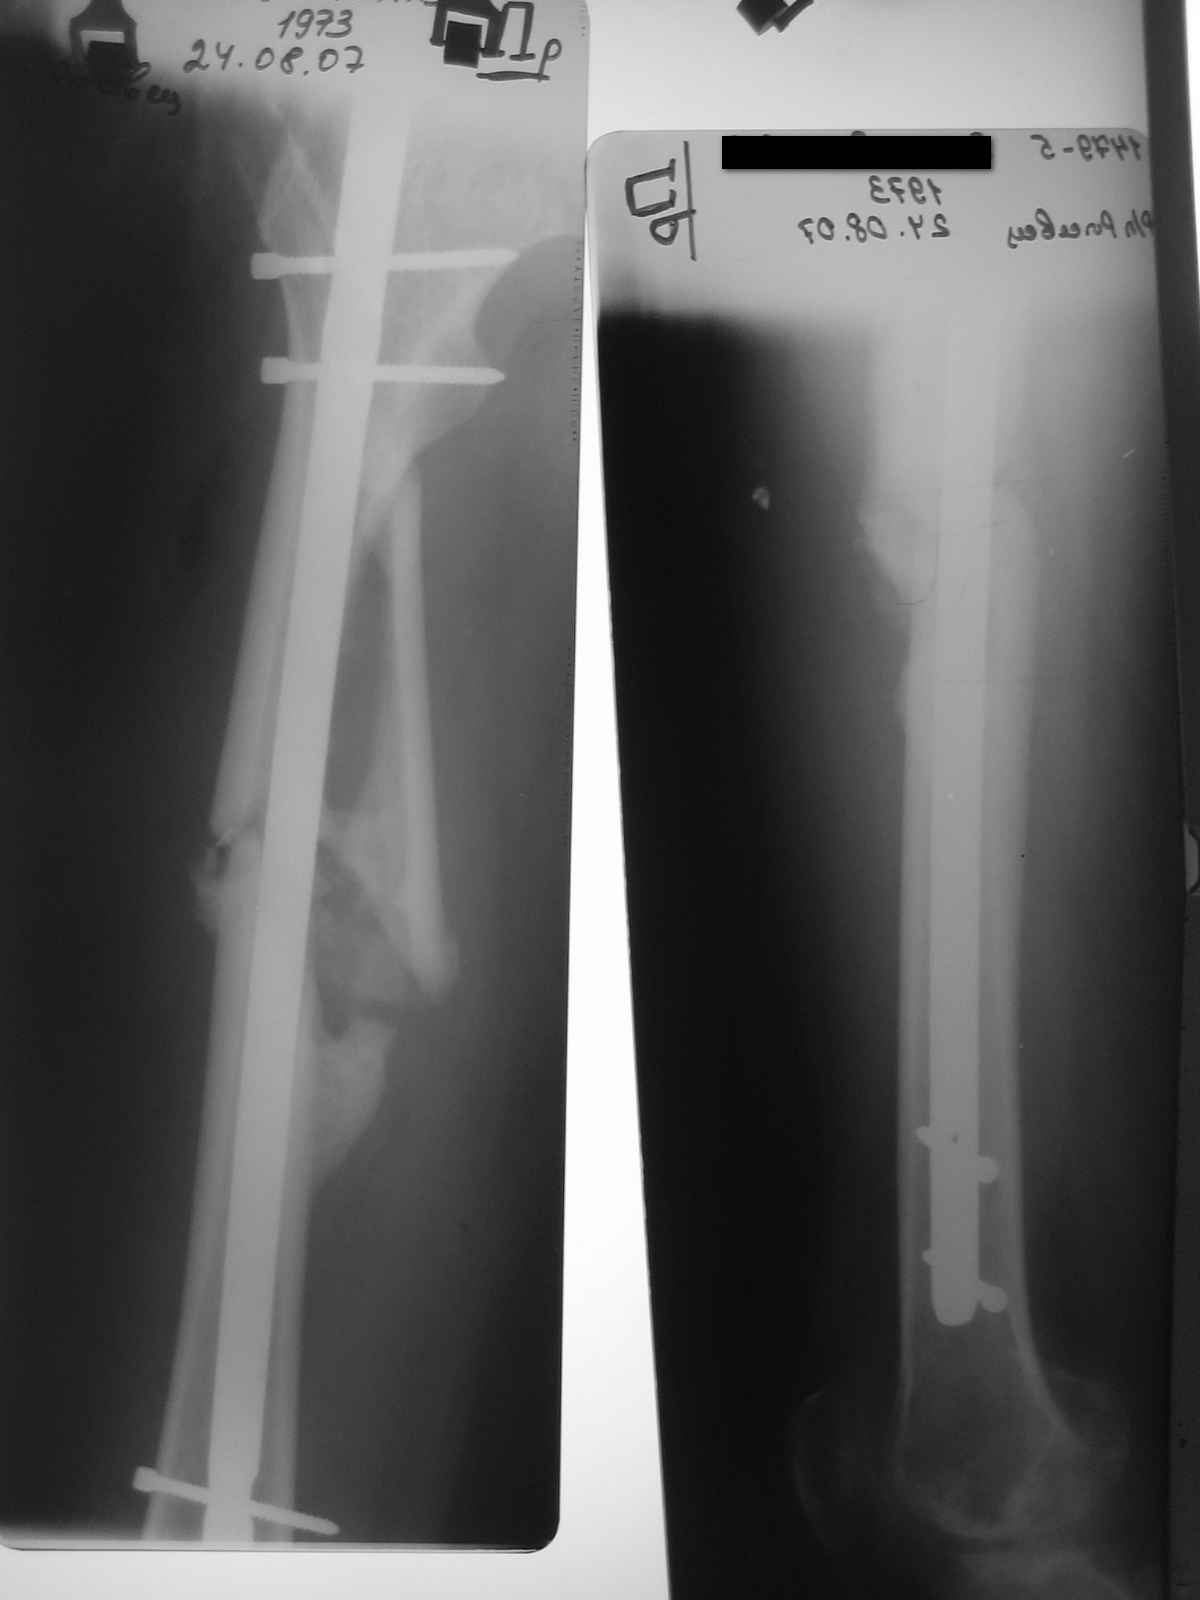

уважаемые коллеги, поступил пациент, через 6 месяцев после травы, который лечлся скелетным вытяжением на районе 3 месяца

затем гипс еще 1,5 месяца, дозированная нагрузка через 3,5 месяца после травмы. Дней 5 назад поскользнулся в ванной, почувствовал боль в бедре, появилась деформация. Оперирован у нас, произведен остеосинтез блокирующим стержнем ,перелом не открывался, был "доломан" на столе. меня интересует вариант вальгирования гвоздя в этом случае. И по-вашему какие ерспективы у этого клиента?

Учитывая отсутствие медиальной стенки на большом протяжении, действительно, мог быть варус при латеральном заходе. Но удалось вполне неплохо справиться, можно поздравить. Из дополнительных мер - точку входа надо делать чуть медиальнее, и можно ввести спицу спереди назад над дефектом, чтобы гвоздь оттеснить к латеральной стенке канала.